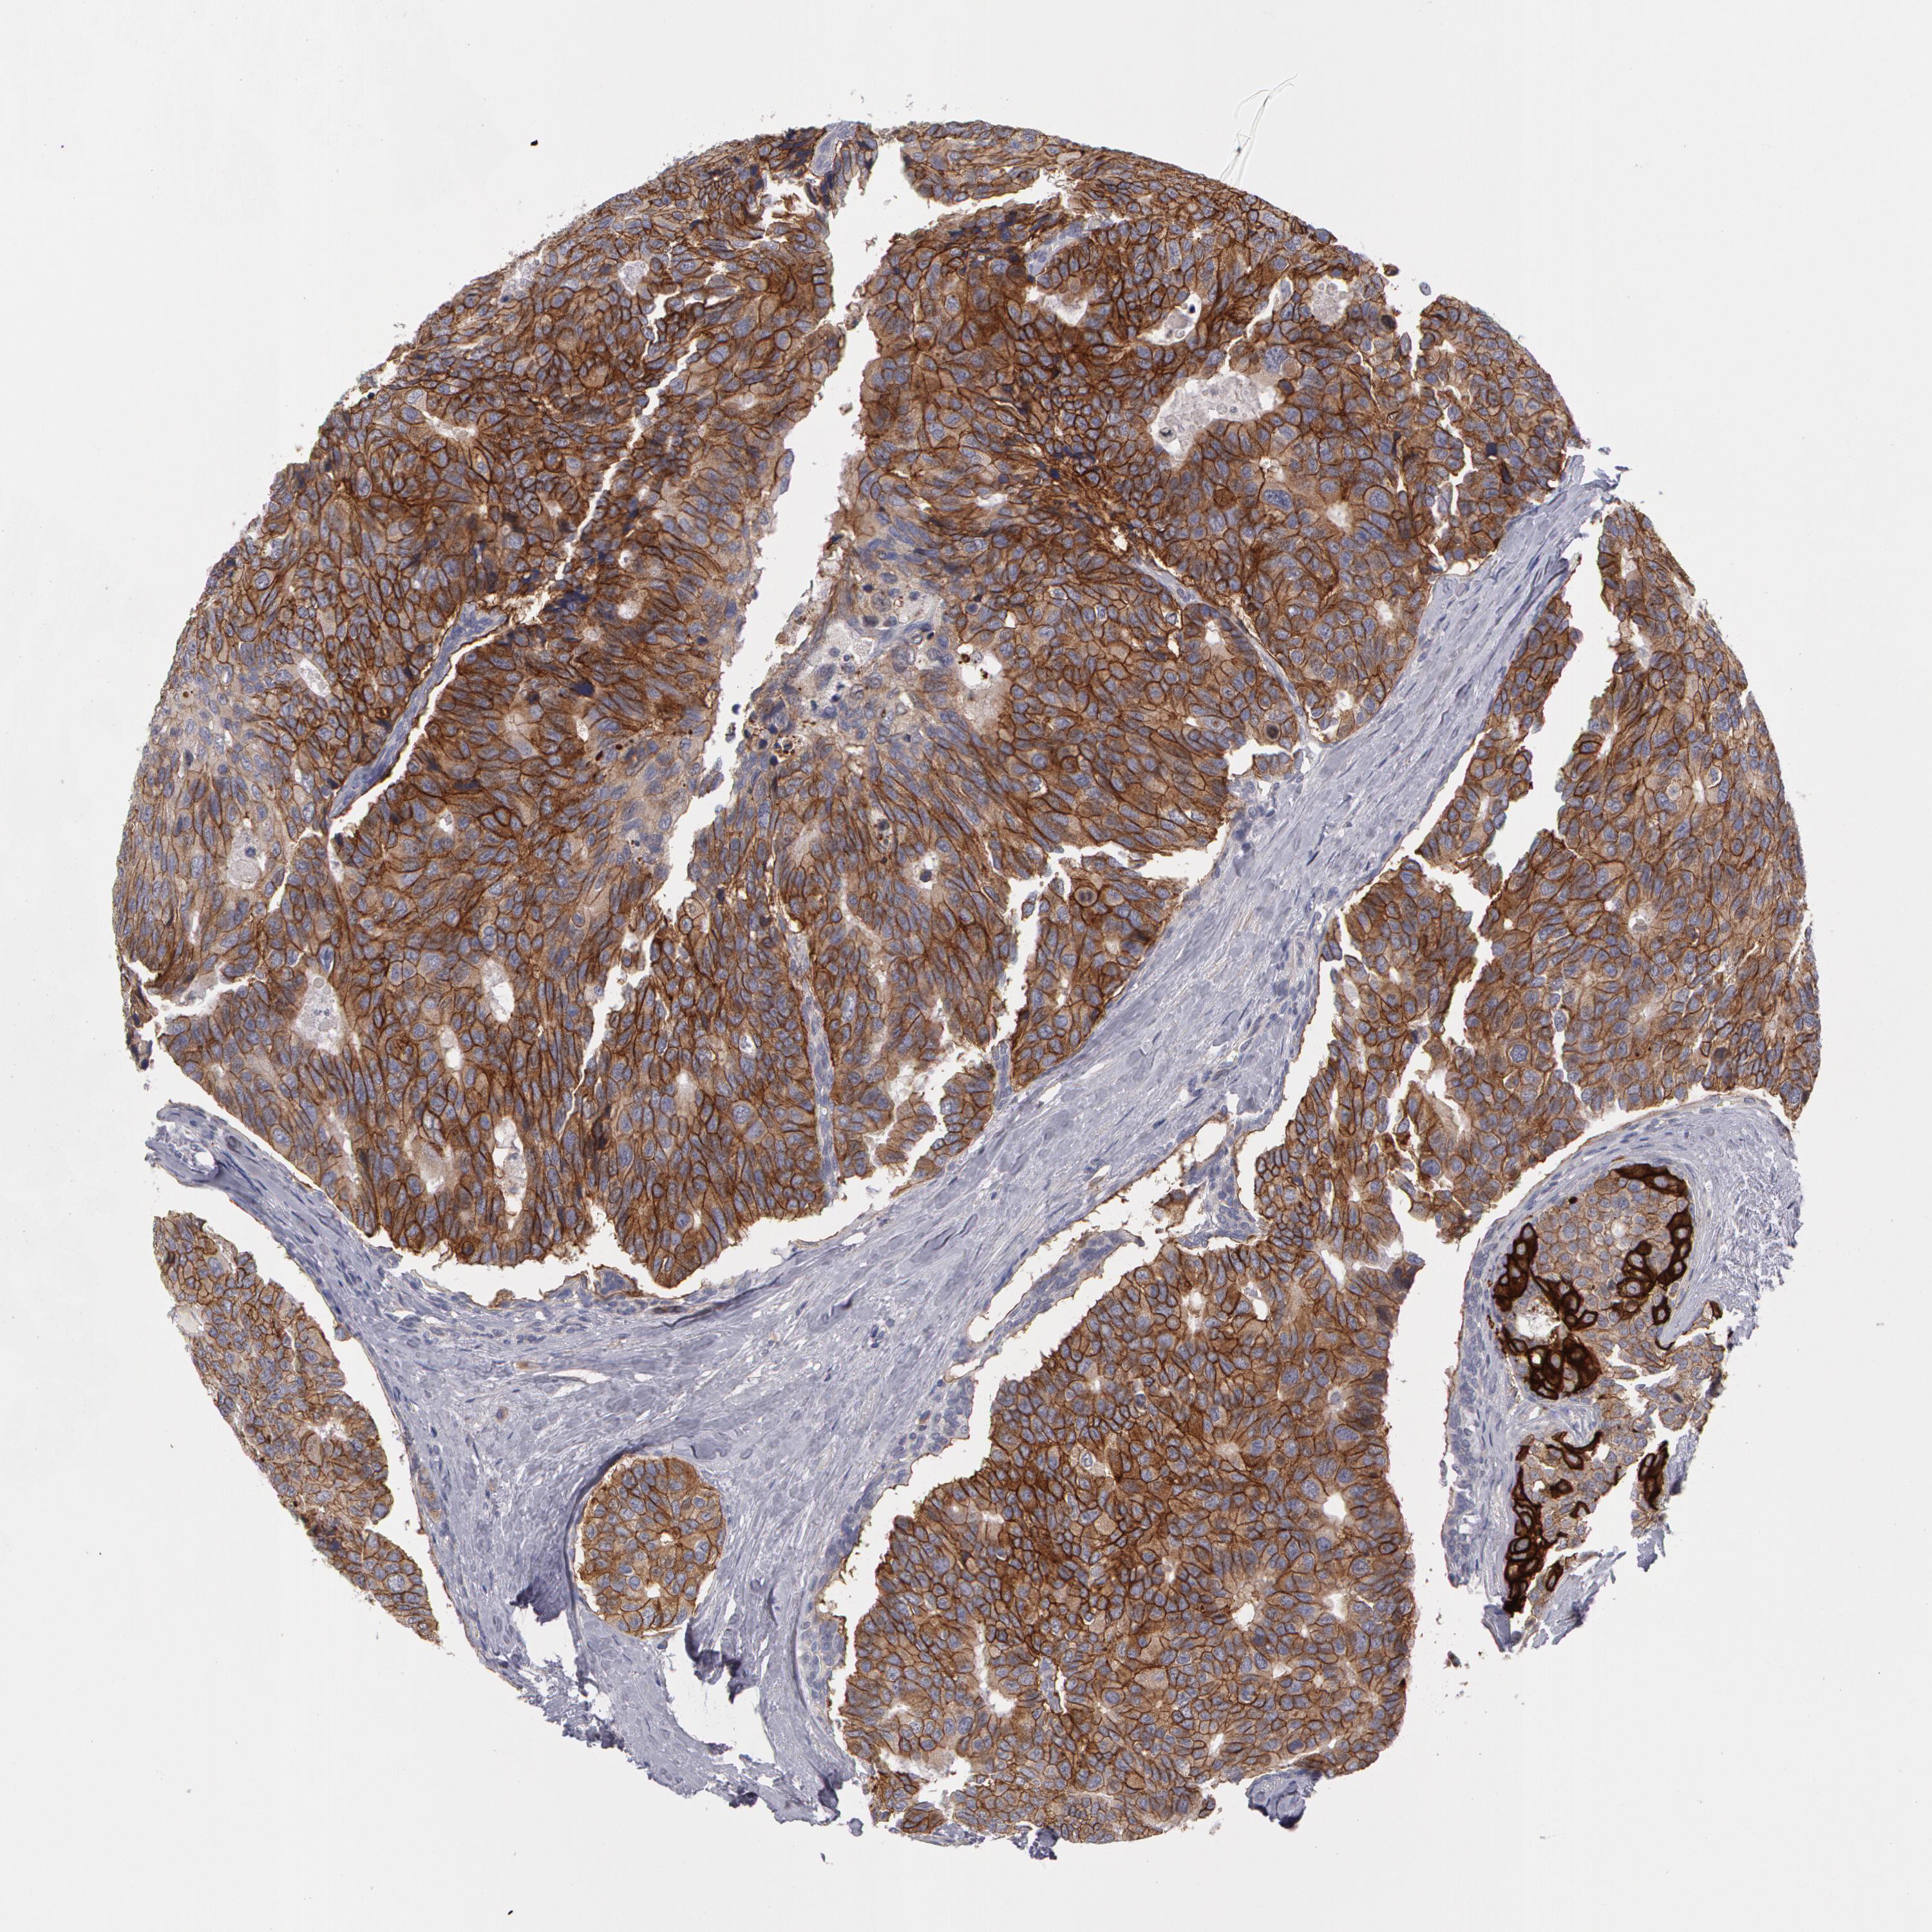

CANCER BREAST CANCER Show tissue menu

BRCA TCGA BRCA VALIDATION PROTEIN EXPRESSION

ANTIBODIES

AND

VALIDATION